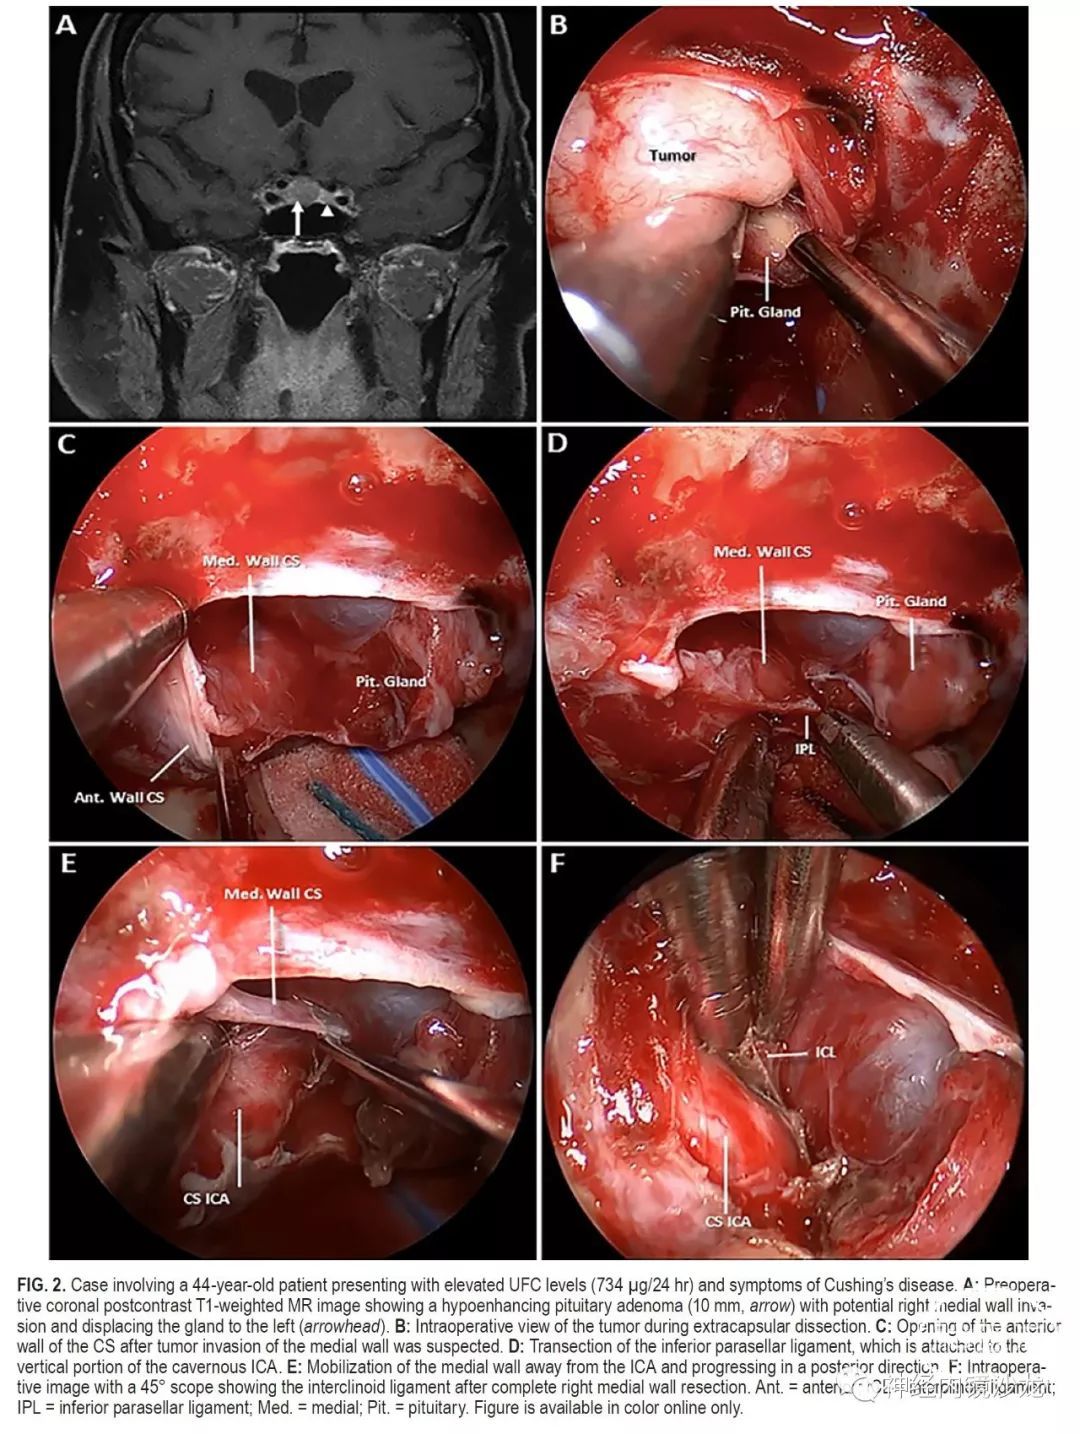

目的:垂体腺瘤常侵袭海绵窦(CS)的内侧壁,但由于存在血管和颅神经损伤的风险,通常不能外科手术切除。本研究的目的是报告一组大宗采用基于解剖学基础、分步选择性地手术切除海绵窦内侧壁的侵袭性垂体腺瘤病例的手术结果。

方法:对作者所在机构数据库进行了研究分析,筛选术中发现单纯侵犯内侧壁且采用内镜经鼻入路选择性切除海绵窦内侧壁的垂体腺瘤病例。排除侵袭海绵窦超出内侧壁的病例。对患者的并发症、切除率和缓解率进行评估。

结果:50例患者符合本研究的条件,15例(30%)非功能性腺瘤和35例(70%)功能性腺瘤;包括16例生长激素、10例催乳素和9例促肾上腺皮质激素(ACTH)腺瘤。非功能性腺瘤的平均肿瘤大小为2.3cm,功能性腺瘤的平均肿瘤大小为1.3cm。放射学检查,11例(22%)为Knosp 1级,23例(46%)Knosp 2级,16例(32%)Knosp 3级。根据术中判断和术后MRI,所有病例均实现肿瘤全切。对于功能性腺瘤患者,平均随访时间为30个月(范围4-64个月),对于非功能性腺瘤患者,平均随访时间为16个月(范围4-30个月)。根据最后一次随访结果,34例(97%)功能性腺瘤未采用辅助治疗即获得完全生化缓解(使用现行标准)。非功能性腺瘤的患者,未见影像学复发。50名患者中共切除了57侧内侧壁。组织学证实,93%的非功能性腺瘤和83%的功能性腺瘤中存在内侧壁侵袭。没有死亡或颈内动脉损伤病例,平均失血量为378ml。4名患者(8%)出现新发短暂性颅神经麻痹,其中2名患者需要再次手术清除血凝块和脂肪填塞物。未出现永久性颅神经麻痹。

结论:海绵窦内侧壁可以安全有效地切除,并发症低,完全切除和症状缓解率极佳。这种基于解剖学的手术技术的长期疗效,需要更多随访数据进一步确定。该技术只能由非常有经验的鼻内镜颅底团队进行。